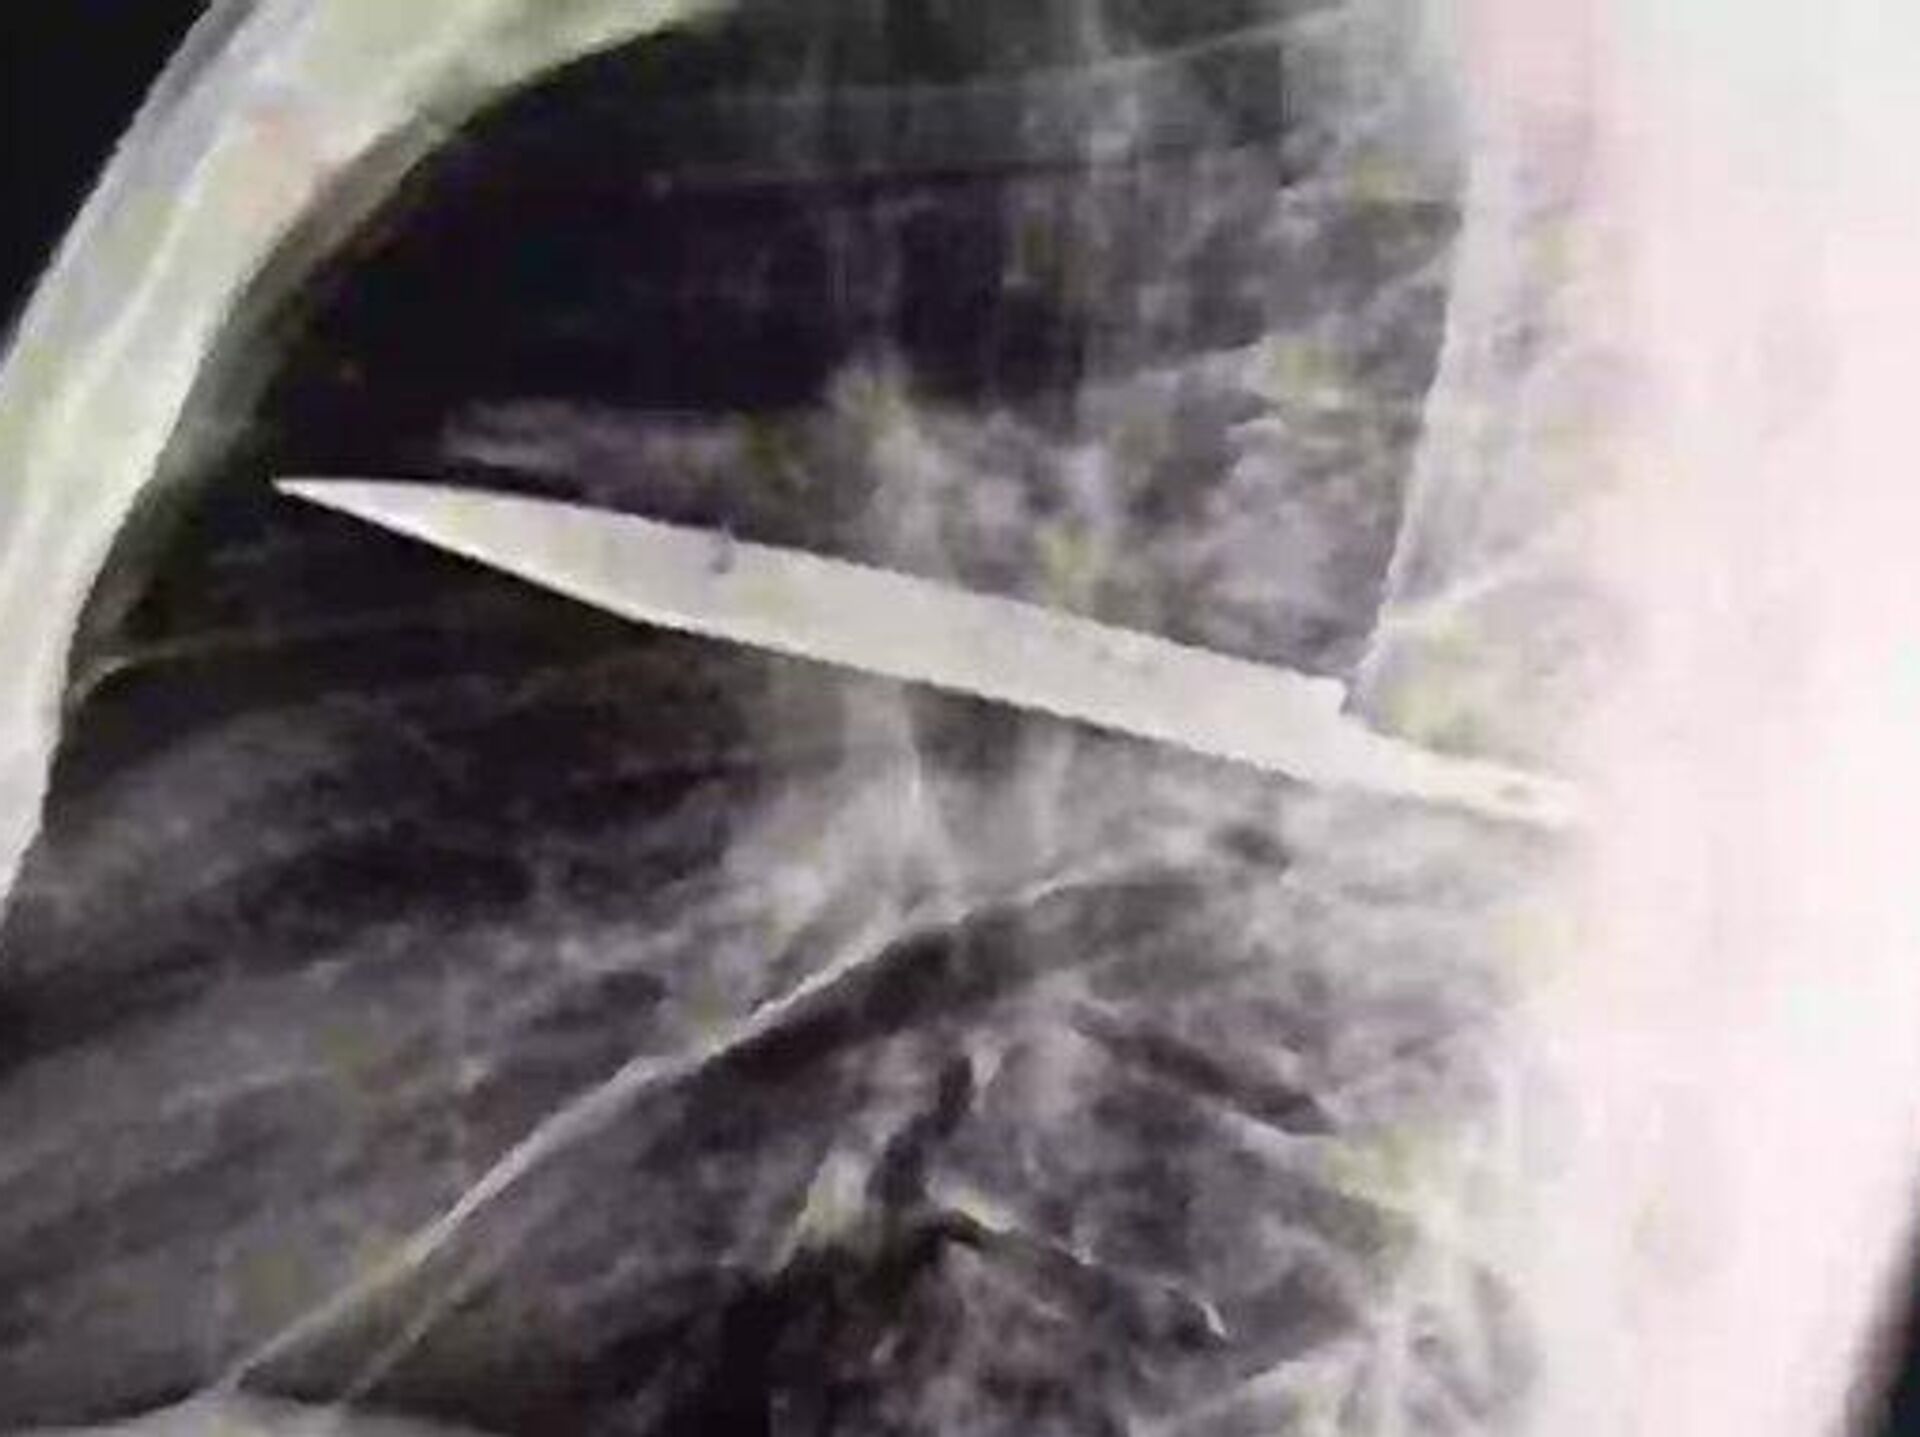

13:58 20.08.2025 (güncellendi: 14:53 20.08.2025) Tanzanya’da 44 yaşındaki bir adam, göğsünden irin gelmesi üzerine hastaneye gitti. Yapılan röntgen, inanılması güç bir gerçeği ortaya çıkardı. Göğsünde sekiz yıldır saplı bir bıçak olduğu anlaşıldı.

Tanzayalı 44 yaşındaki Adam, sağ göğsünden irin akmaya başlayınca enfeksiyon kaptığını düşündü. Ancak doktorlar muayene sırasında durumun çok daha farklı olduğunu fark etti. İlk başta sağlıklı görünen adamın röntgeninde göğsünde büyük bir bıçak tespit edildi.

Hasta, doktorlara sekiz yıl önce bir kavgaya karıştığını ve vücudunun birçok yerinden kesikler aldığını anlattı. O dönem uzak bir bölgede yaşadığı için yalnızca yüzeysel tedavi gördü ve hiç röntgen çektirmedi. Olayın ardından yıllarca göğsünden irin akana kadar hiçbir belirti göstermedi.

Doktorlar hemen ameliyat kararı aldı. Bıçak başarıyla çıkarıldı ve adam sadece 10 gün içinde taburcu edildi. Uzmanlar bunun büyük bir şans olduğunu belirterek, 'Bu kadar uzun süre bıçakla yaşamak ölümcül sonuçlar doğurabilirdi' dedi.

Tıp uzmanlarına göre adamın hayatta kalmasının sebebi, vücudunun bıçağı koruyucu bir kapsül içine alarak iltihaplanmayı geciktirmesiydi. Ancak zamanla bu sistem zayıfladı ve irin akmasıyla birlikte ciddi komplikasyonlar başladı.